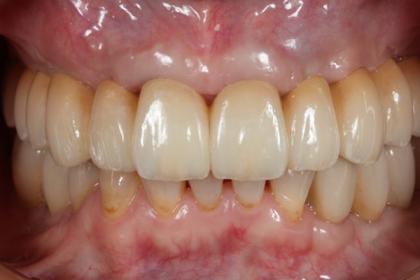

総合的な審美治療

Before

After

基礎データ 30代女性

治療期間 2003〜2009年

治療費 144万(矯正治療の費用は他院にて請求)

主な治療 歯列矯正・抜歯・軟組織移植・クラウンブリッジ補綴

治療計画 不正なクラウンを除去、保存できない歯を抜歯し、正しい噛み合わせを作れるように外科矯正を含んだ矯正治療を行う。

矯正治療後、前歯部の吸収した組織を増大し、クラウンブリッジを作成した。